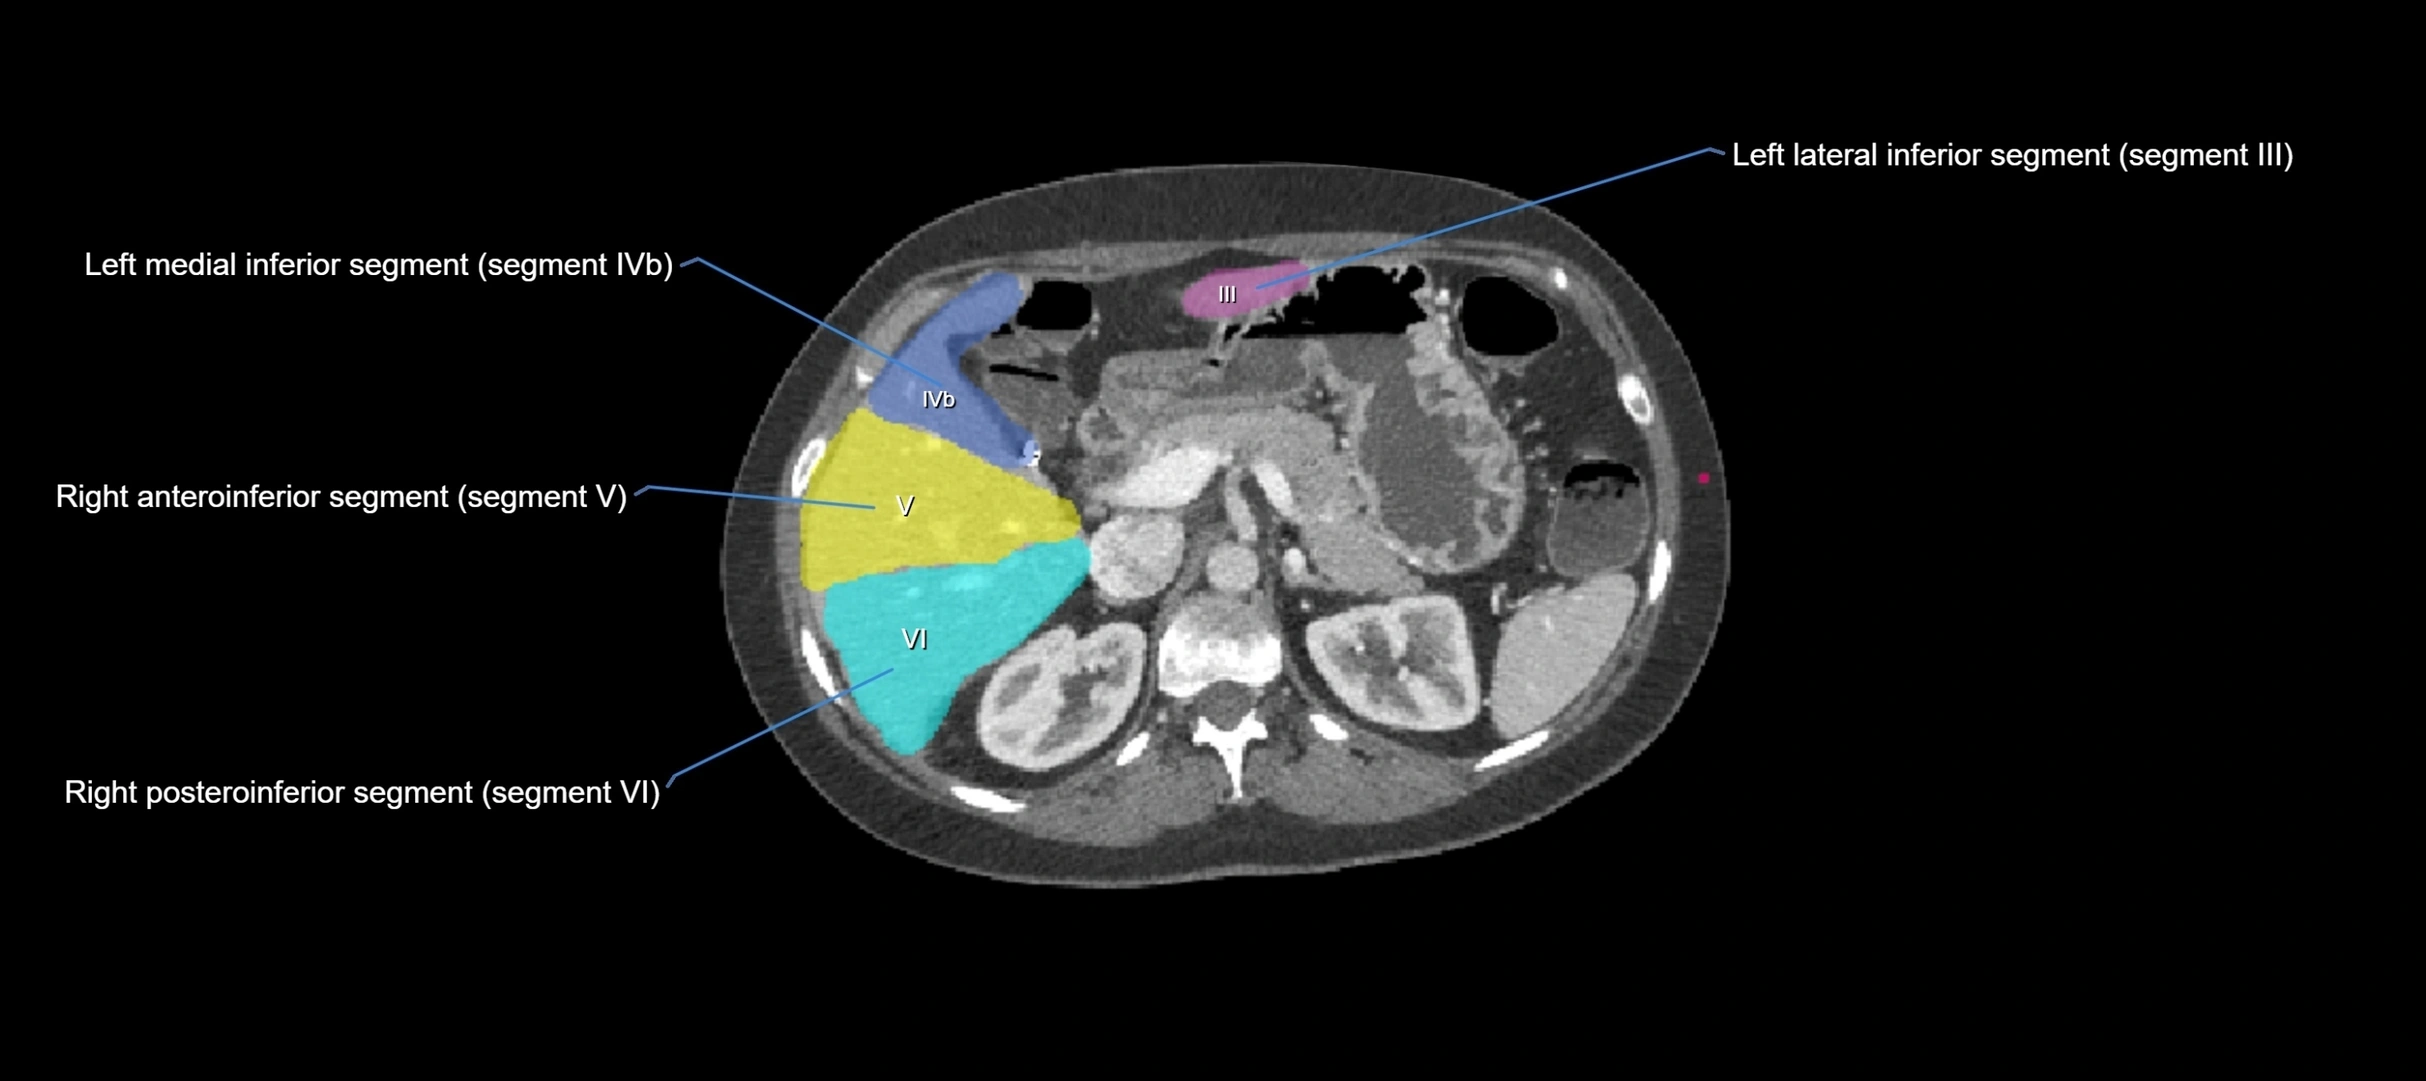

CT Image

image